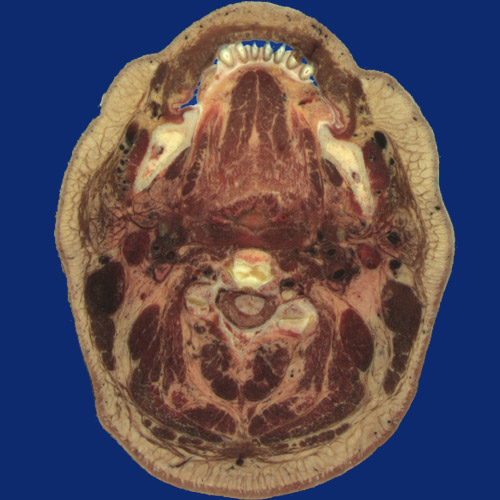

Identify the following regions in the image above: Orbicularis oris - Depressor anguli oris - Mandible with teeth - Masseter - Medial pterygoid - Facial vein - Submandibular gland - Parotid gland - Retromandibular vein - Posterior auricular vein - Posterior digastricus - Internal jugular vein and Internal carotid artery - Genioglossus - Mylohyoid - Pharynx - Pharyngeal tonsils - Pharyngeal constrictor muscle - Sternocleidomastoid - Levator scapulae - Splenius cervicis - Trapezius - Splenius capitis - Semispinalis capitis - Semispinalis cervicis & multifidus - Intervertebral disk - Spinal cord